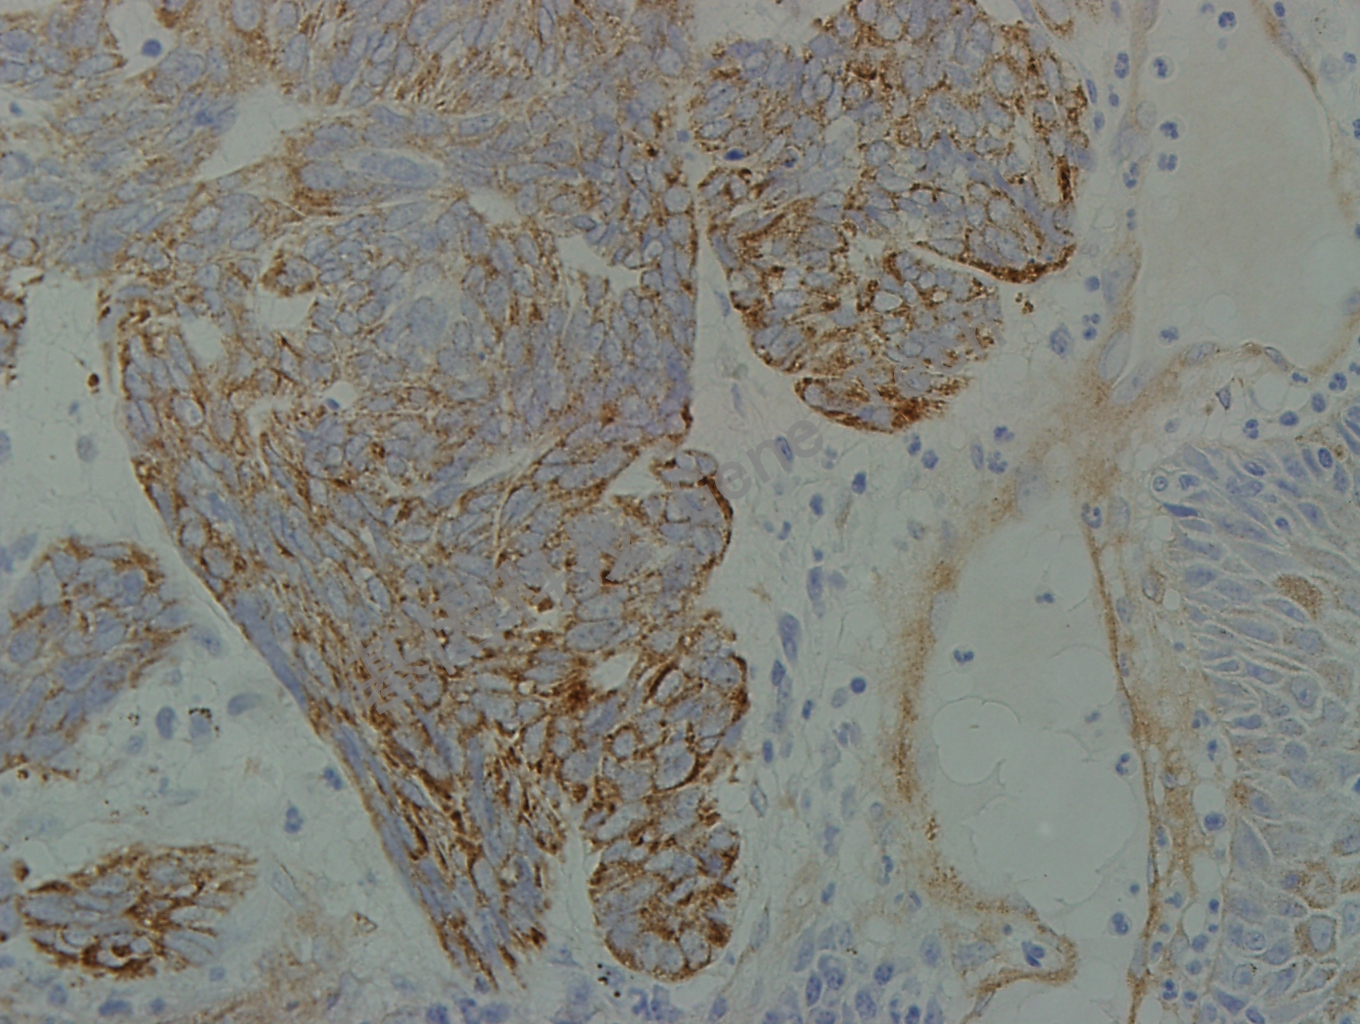

Laminin 鼠抗人 Laminin 抗體試劑(免疫組織化學(xué))

| 預(yù)處理:蛋白酶K修復(fù) | 陽性部位:基底膜 | 陽性對照:皮膚 |

| 簡介:Laminin(層粘連蛋白)是基底膜的重要組成成分,是基底膜中的IV型膠原蛋白和周圍基質(zhì)中的糖胺聚糖的連接橋梁。在軟組織中,內(nèi)皮細胞、平滑肌和施萬細胞周圍有完整的基底膜形成。腫瘤的浸潤和轉(zhuǎn)移與其遭到破壞相關(guān)。抗層粘連蛋白和層粘連蛋白的抗體可以用于標記基底膜,有助于研究在腫瘤浸潤和轉(zhuǎn)移時的基底膜的變化。 | ||

| 皮膚石蠟切片,用 Laminin(GT2222)染色,細胞漿陽性,DAB 顯色。 | ||